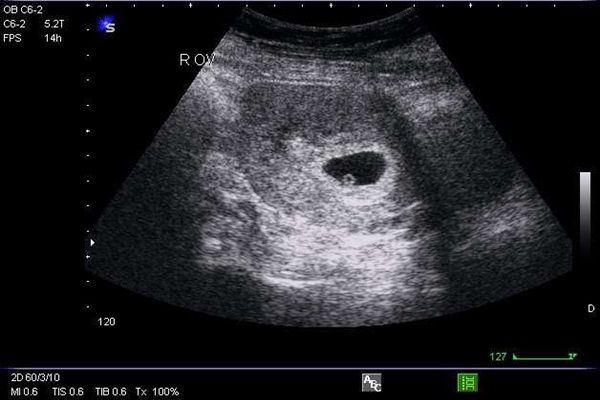

Yên tâm em bé phát triển tốt, khỏe mạnh xem ảnh siêu âm không cho coi nè

Bang_Chanie: cập nhật tình hình bé Su: bé khỏe mạnh phát triển tốt đã nghe thấy tim thai<( ˙꒳​˙ )╯